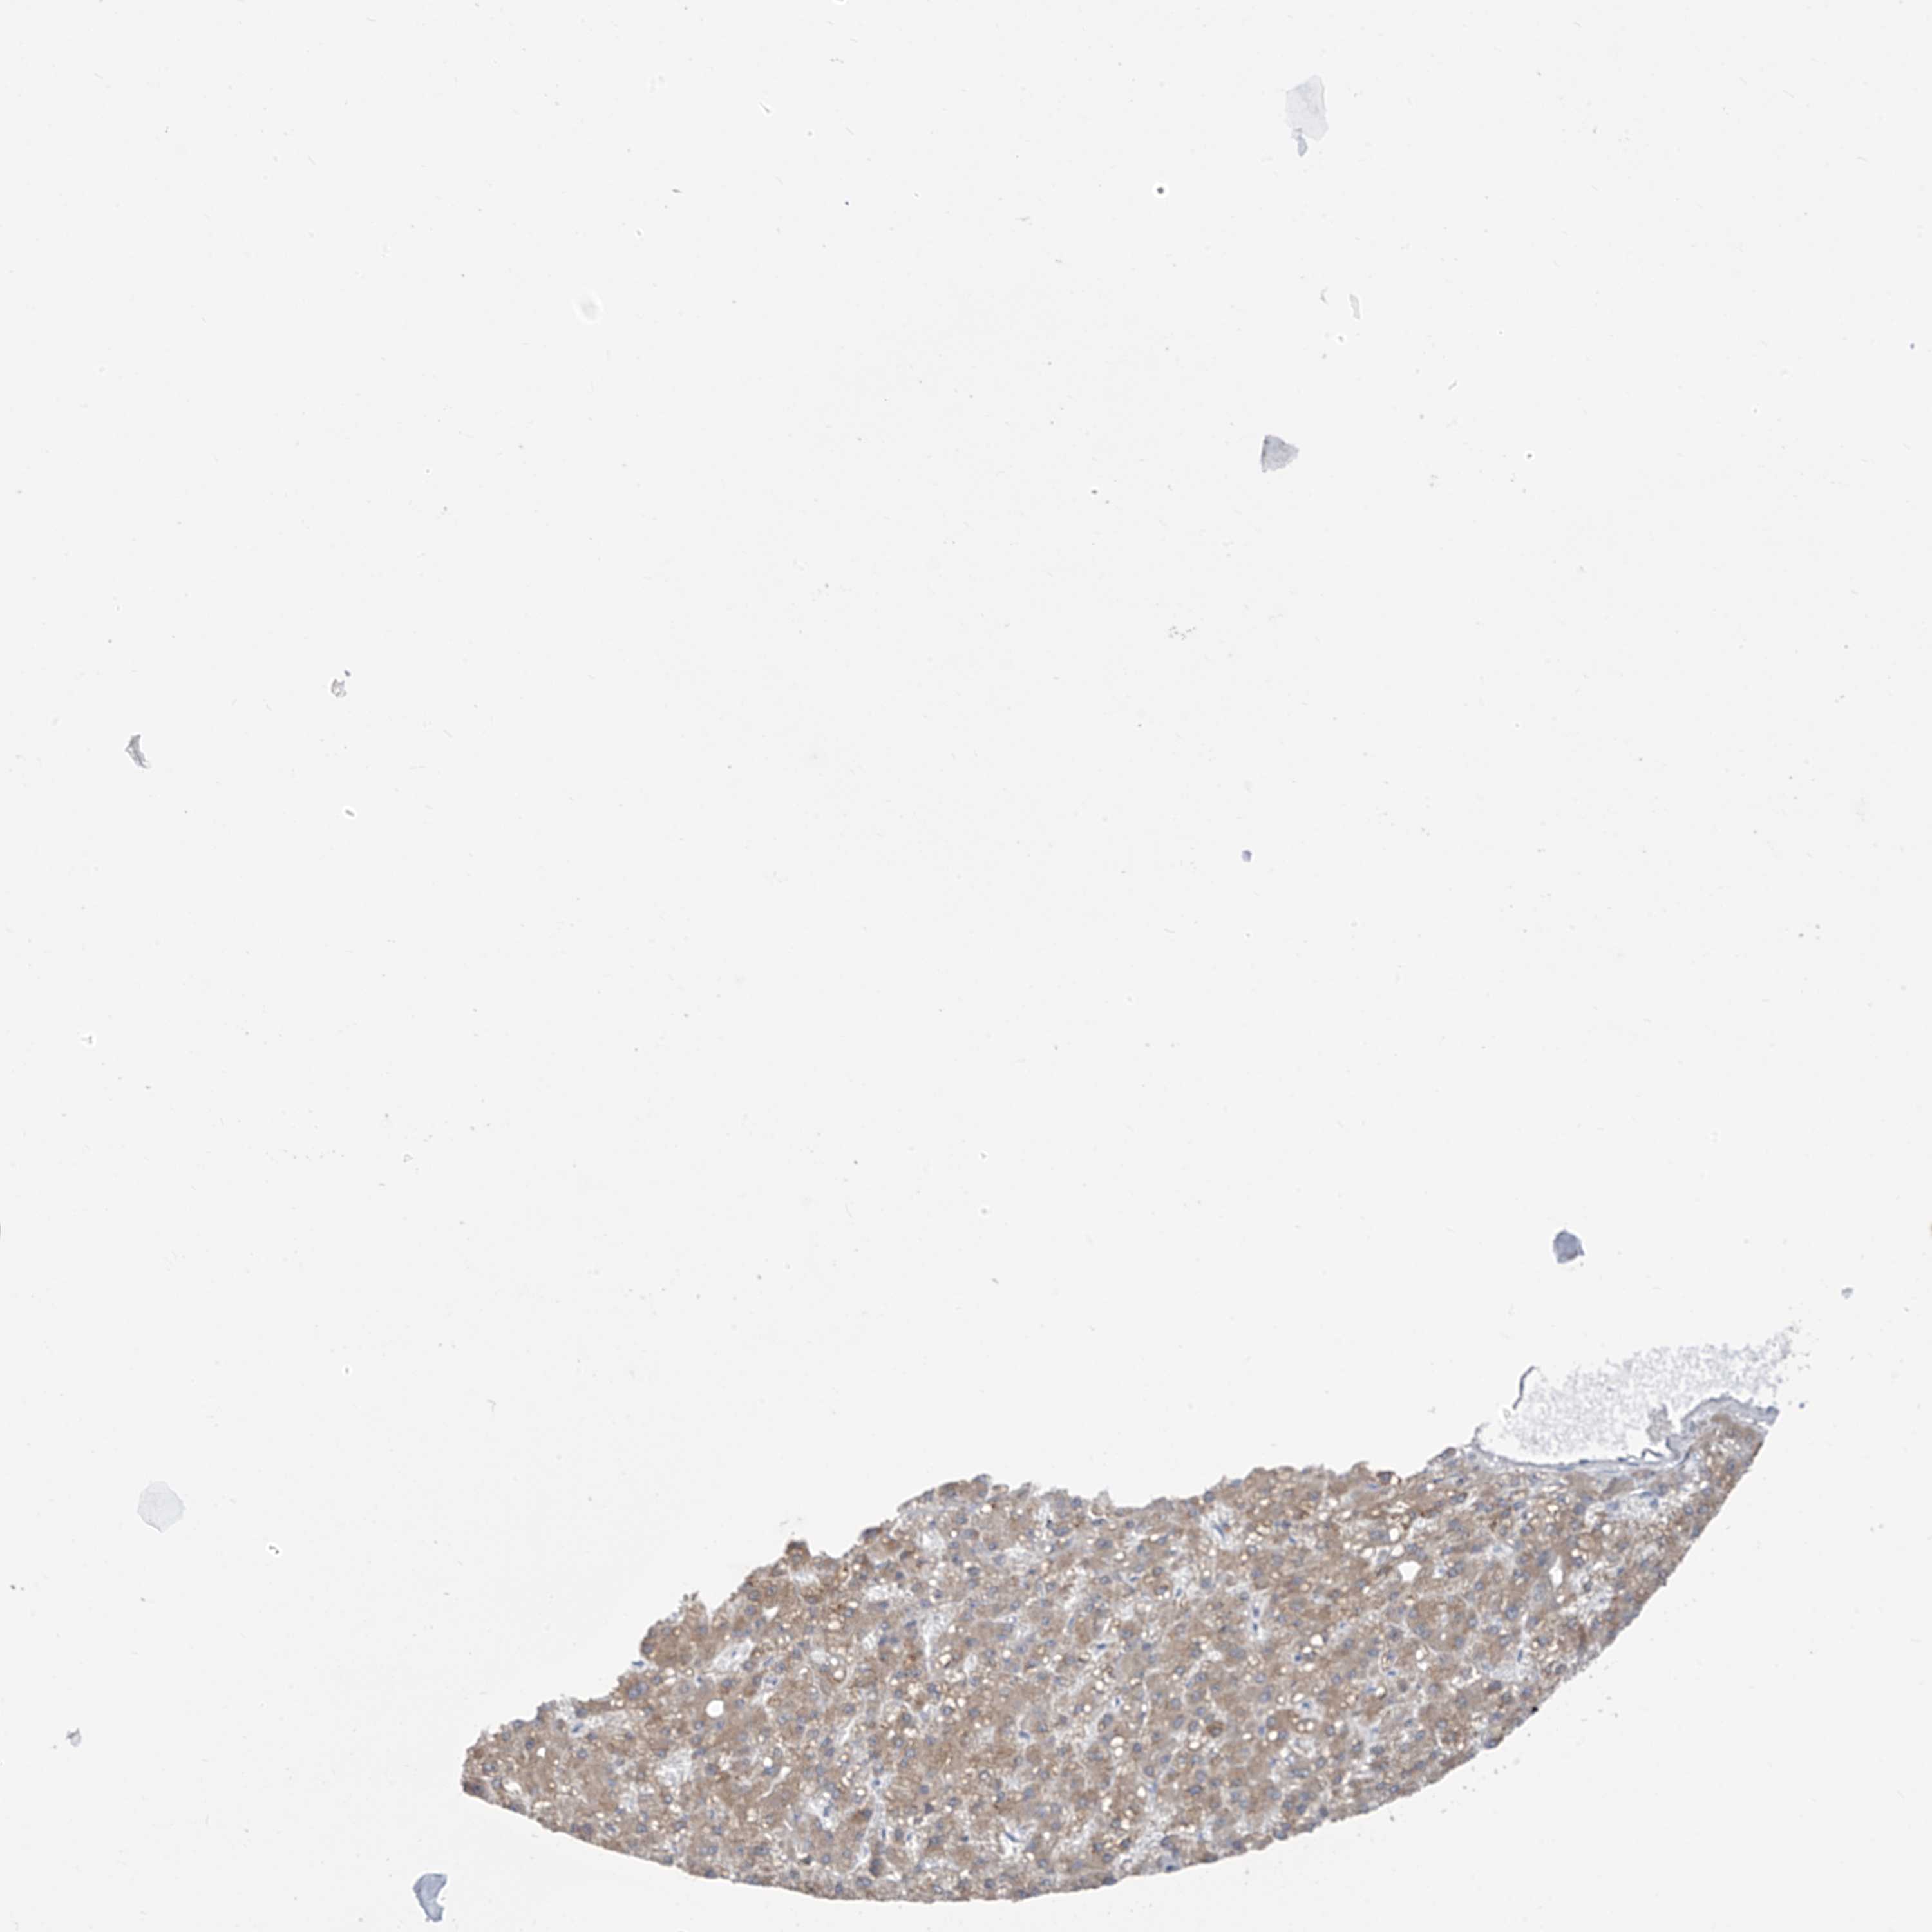

LIVER CANCER - Protein expressioni

A mouse-over function shows sample information and annotation data. Click on an image to view it in a full screen mode. Samples can be filtered based on level of antibody staining by selecting one or several of the following categories: high, medium, low and not detected. The assay and annotation is described here.

Note that samples used for immunohistochemistry by the Human Protein Atlas do not correspond to samples in the TCGA dataset.

Antibody stainingi

Antibody staining in the annotated cell types in the current human tissue is reported as not detected, low, medium, or high, based on conventional immunohistochemistry profiling in selected tissues. This score is based on the combination of the staining intensity and fraction of stained cells.

Each image is clickable and will lead to virtual microscopy that enables deeper exploration of all samples and also displays staining intensity scores, fraction scores and subcellular localization as well as patient and tissue information for each sample.

Antibody HPA029122

Staining

High

Medium

Low

Not detected

Intensity

Strong

Moderate

Weak

Negative

Quantity

>75%

75%-25%

<25%

None

Location

Nuclear

Cytoplasmic/membranous

Cytoplasmic/membranous,nuclear

Cholangiocarcinoma

Carcinoma, Hepatocellular, NOS